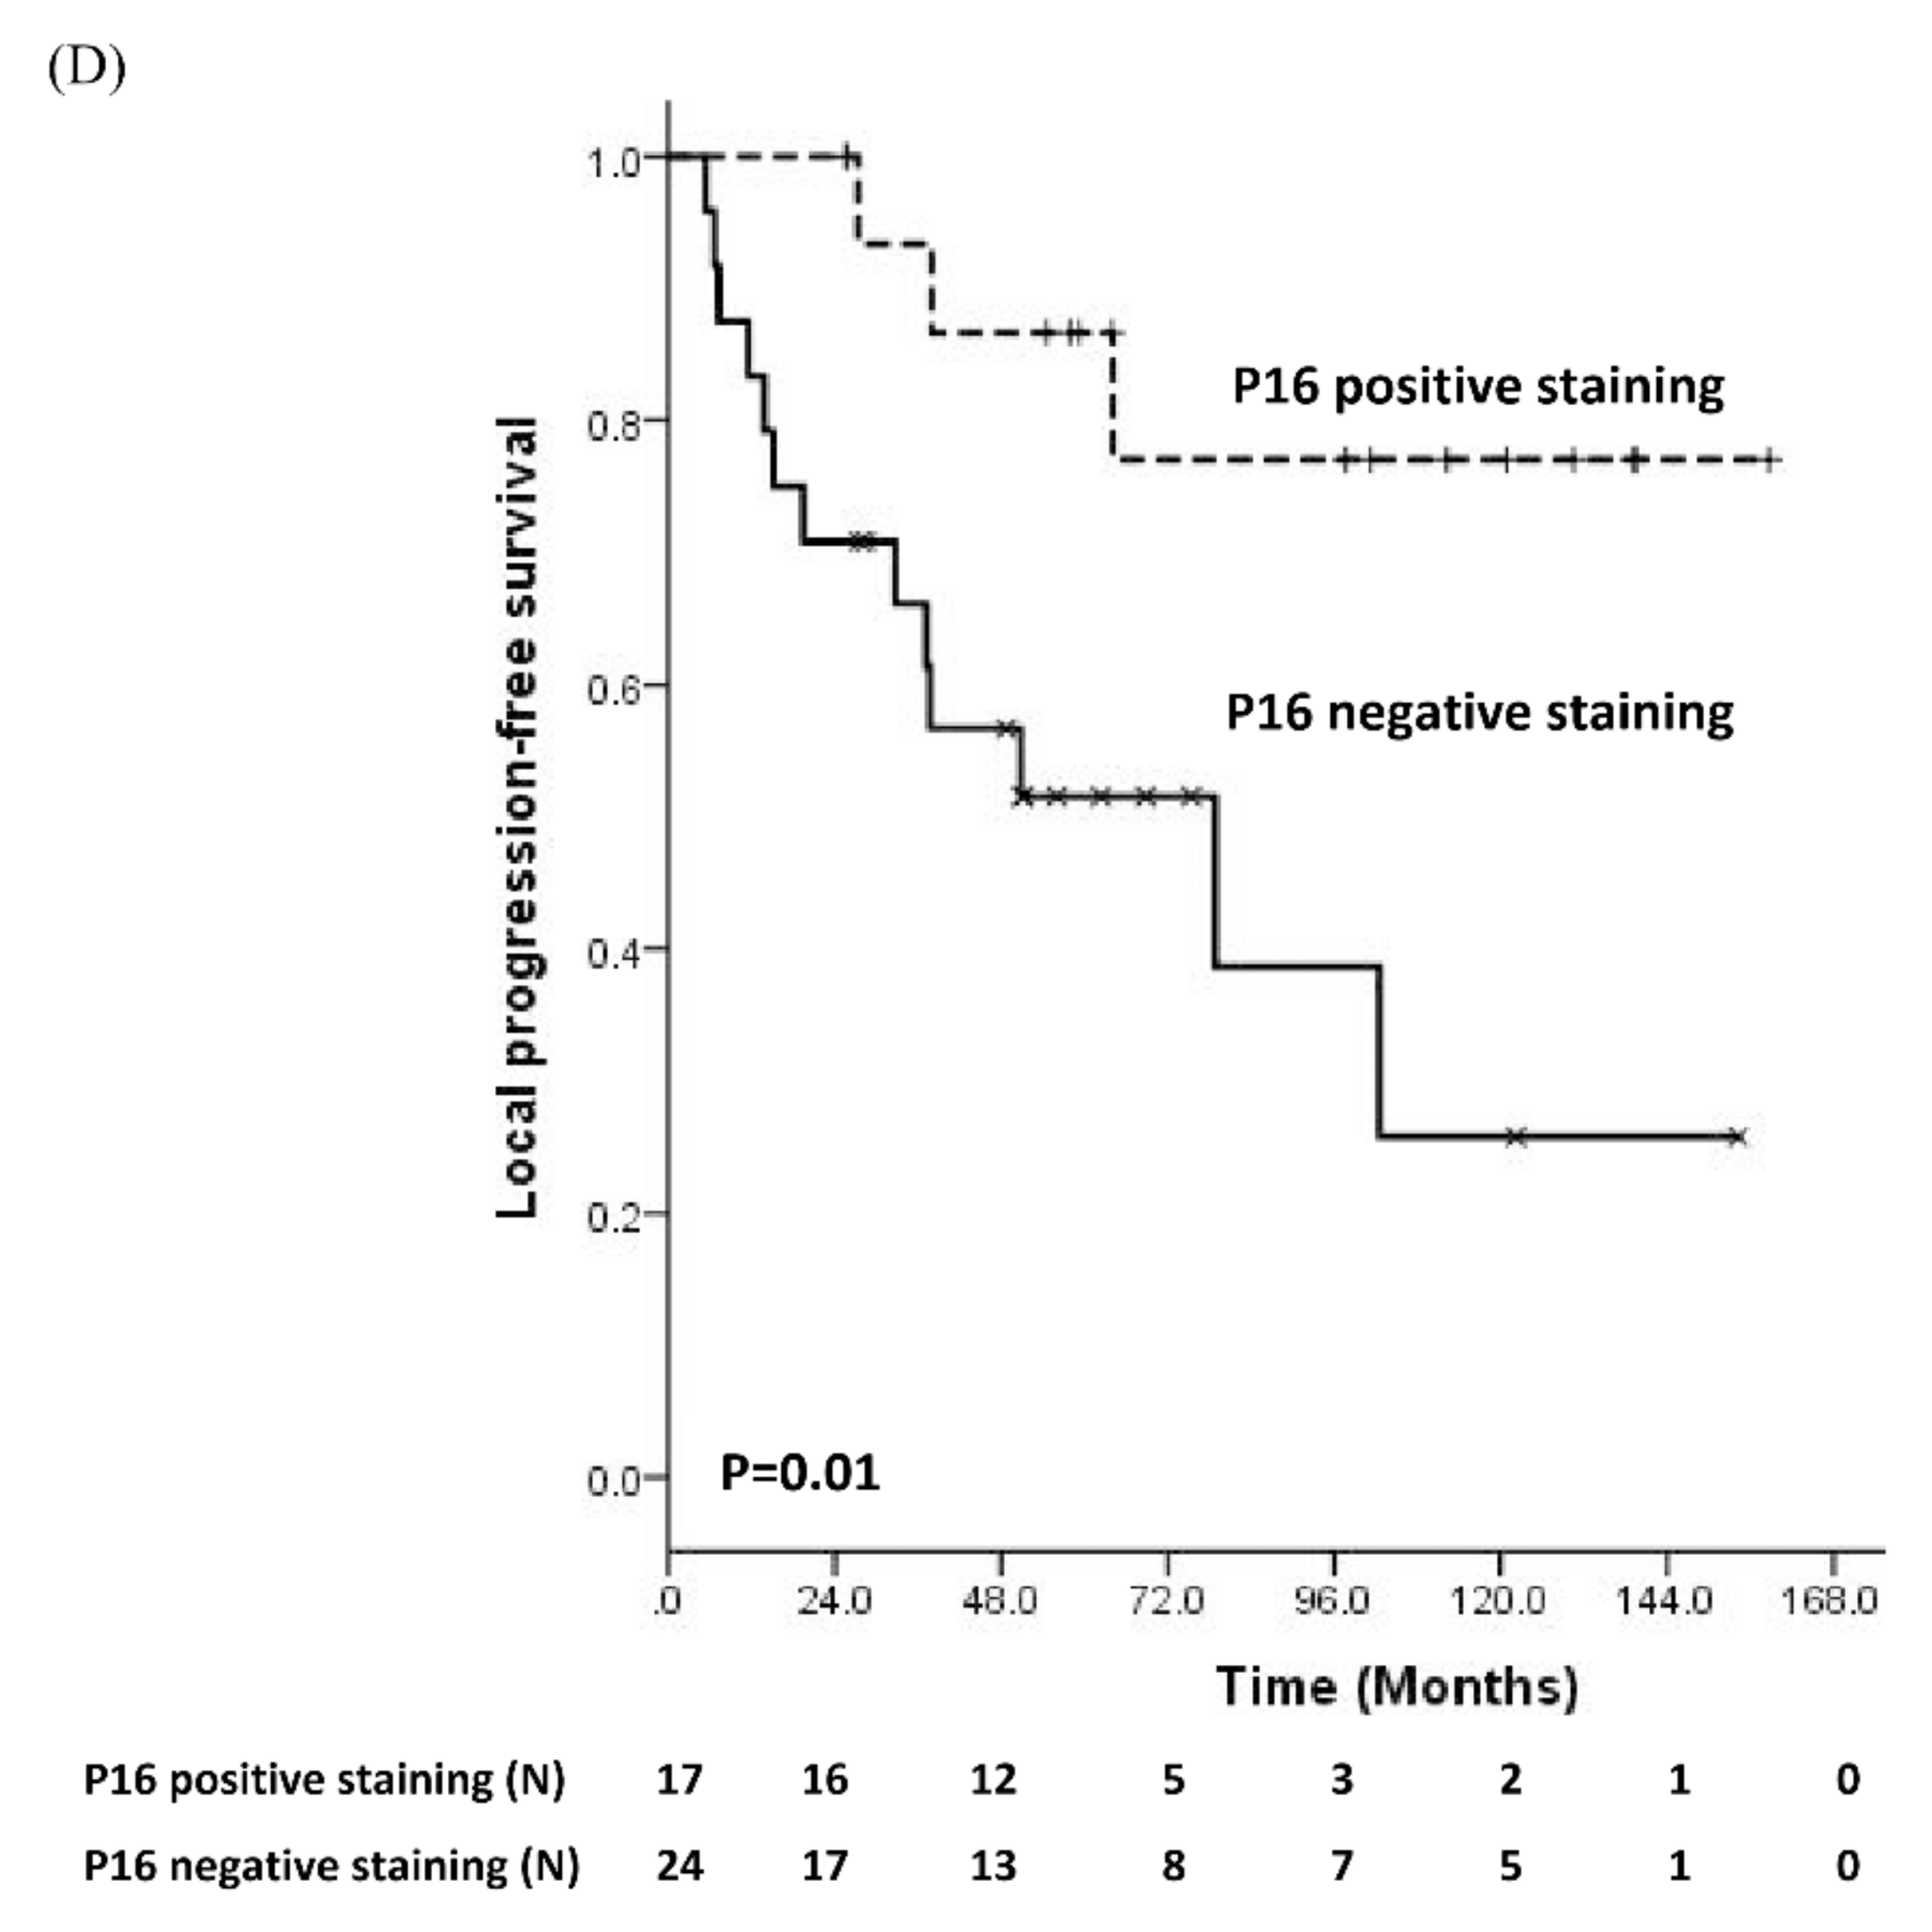

3.2. Prognostic Significance of Molecular Biomarker

3.3. Comparisons of Immunostaining of NFκB between Pre-Treatment Samples and Recurrent Samples